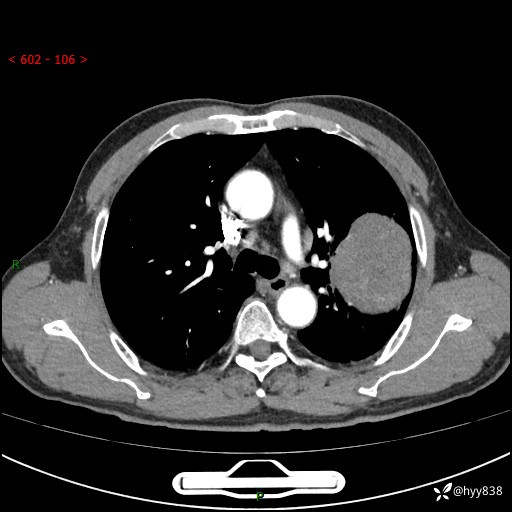

68岁/男,发现左下肺占位5天。如此大的肿块,患者竟然没有症状---结果公布~

【患者信息】:68岁/男

【主诉】:检查发现左下肺占位5天。

【现病史及既往史】:患者于4天前外院行“经尿道钬激光碎石术”,住院期间胸部CT检查发现左下肺肿块,患者平素无明显咳嗽咳痰,无心慌、胸闷、胸痛、呼吸困难、低热、盗汗,无头痛、头晕,无腹痛、腹胀等不适,现患者为求进一步治疗,遂来我院就诊,以“左下肺肿块”收入我科。 患者自起病以来,精神可,睡眠可,饮食可,大小便正常,体重无明显改变。

【检查】:胸部CT增强扫描